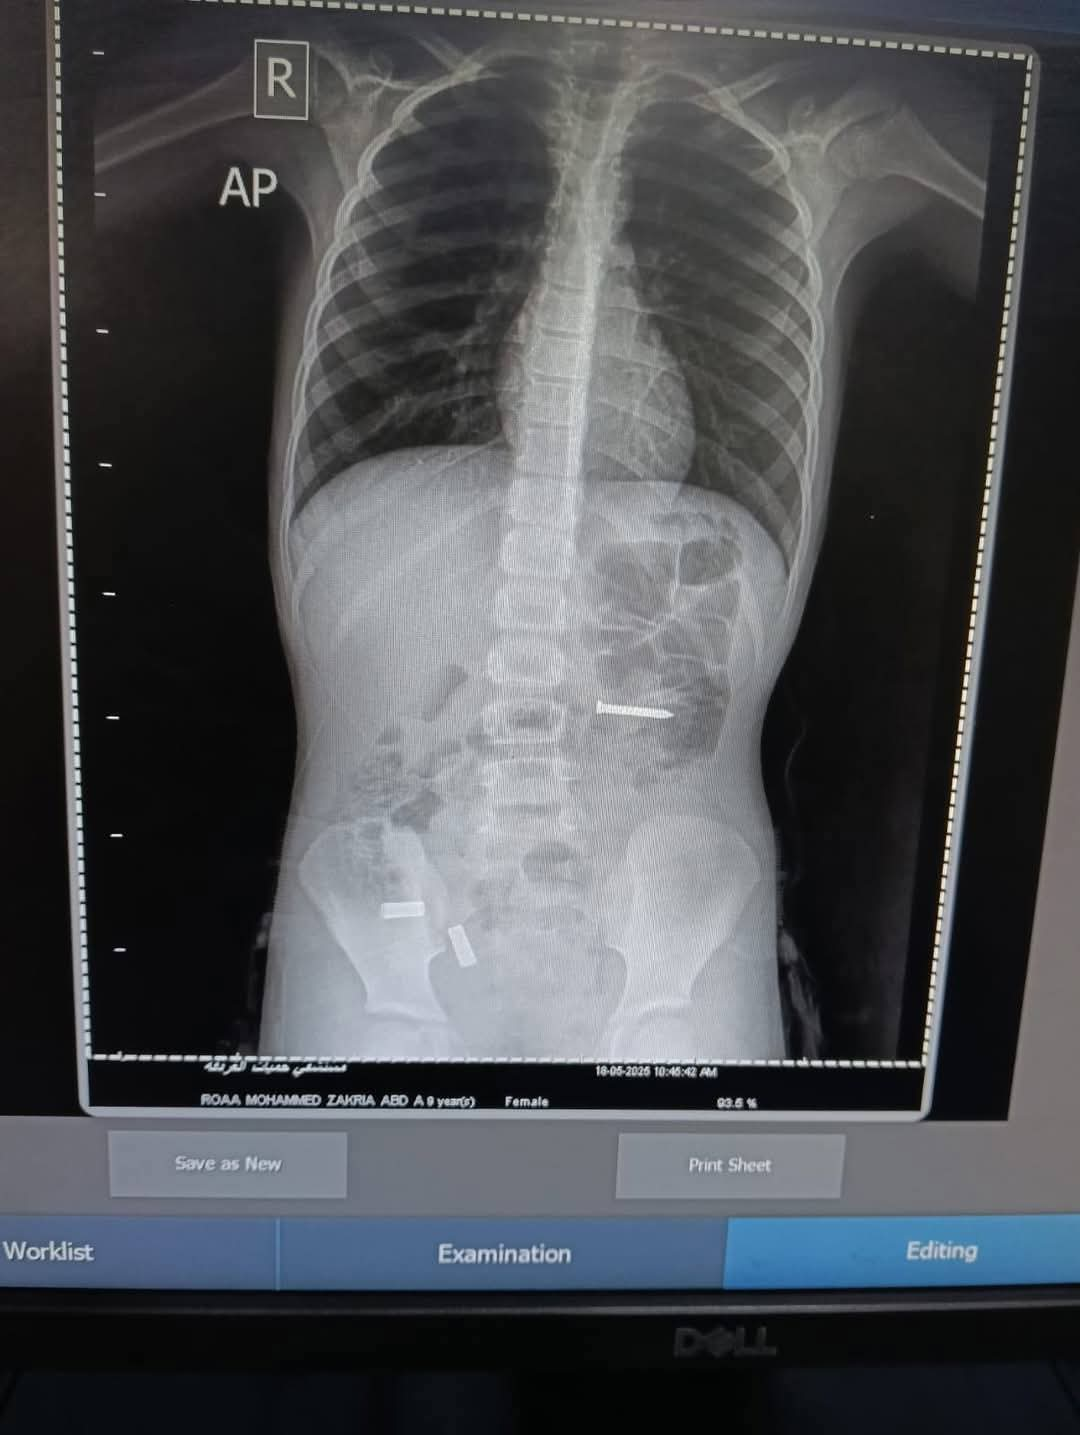

أشعة تظهر وجود مسمار في معدة طفلة

وأثبتت الفحوصات الطبية والأشعة التي تم عملها للطفلة، وجود جسم معدني غريب داخل الأمعاء، وعلى إثره تم تحضيرها للعمليات من قبل قسم المناظير بمستشفى حميات الغردقة.

وتعود الواقعة إلى نجاح فريق قسم المناظير بمستشفى حميات الغردقة، بقيادة استشاري الكبد والجهاز الهضمي والمناظير، الدكتور مصطفى عزت، واستشاري التخدير، الدكتور مصطفى سنبل، باستخراج جسم غريب "مسمار" صلب، طوله 3 سنتيمترات، من معدة طفلة تبلغ من العمر 9 سنوات.

وكشف عزت، في تصريحات خاصة لـ"تليجراف مصر"، أنه فور التأكد من الأشعة بوجود جسم غريب داخل الأمعاء، تم الإجماع على دخول الطفلة للعمليات الفورية.